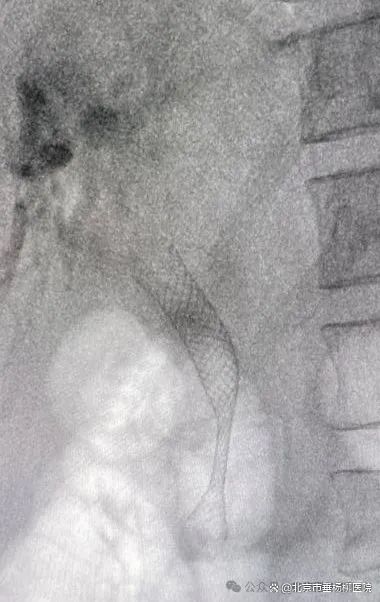

支架置入瞬间,胆汁顺畅流出

支架植入后,下段梗阻处已撑开